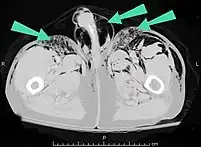

Scanner abdominal (rayons X) d'un patient présentant un emphysème sous-cutané (flèché) | |

Les cas importants d'emphysème sous-cutané sont faciles à diagnostiquer en raison des signes caractéristiques de l'affection. Dans certains cas, les signes sont subtils, ce qui rend le diagnostic plus difficile. L'imagerie médicale est utilisée pour diagnostiquer la maladie ou confirmer un diagnostic établi à l'aide de signes cliniques. Sur une radiographie du thorax, l'emphysème sous-cutané peut être vu comme des stries radiotransparentes dans le modèle attendu du groupe de muscles principaux du pectoral. L'air présent dans les tissus sous-cutanés peut interférer avec la radiographie du thorax, ce qui peut masquer des affections graves comme le pneumothorax. Elle peut également réduire l'efficacité de l'échographie thoracique. D'autre part, comme l'emphysème sous-cutané peut être visible sur les radiographies du thorax avant un pneumothorax, sa présence peut être utilisée pour déduire celle de cette dernière lésion. L'emphysème sous-cutané peut également être observé sur les scanners, les poches d'air apparaissant comme des zones sombres. Le scanner est si sensible qu'il permet généralement de trouver l'endroit exact d'où l'air pénètre dans les tissus mous. En 1994, M. T. Macklin et C. C. Macklin ont publié d'autres aperçus sur la physiopathologie du syndrome de Macklin spontané survenant à la suite d'une grave crise d'asthme. La présence d'un emphysème sous-cutané chez une personne qui semble très malade et fébrile après une crise de vomissements suivie d'une douleur thoracique gauche est très évocatrice du diagnostic du syndrome de Boerhaave, qui est une urgence vitale causée par une rupture de l'œsophage distal. L'emphysème sous-cutané peut être une complication de l'insufflation de CO2 avec la chirurgie laparoscopique. Une augmentation soudaine du CO2 en fin de marée après la hausse initiale qui se produit avec l'insufflation (les 15-30 premières minutes) devrait faire suspecter un emphysème sous-cutané. Il est à noter que l'oxymétrie de pouls et la pression des voies aériennes ne varient pas dans l'emphysème sous-cutané, contrairement à l'intubation endobronchique, au capnothorax, au pneumothorax ou à l'embolie au CO2.